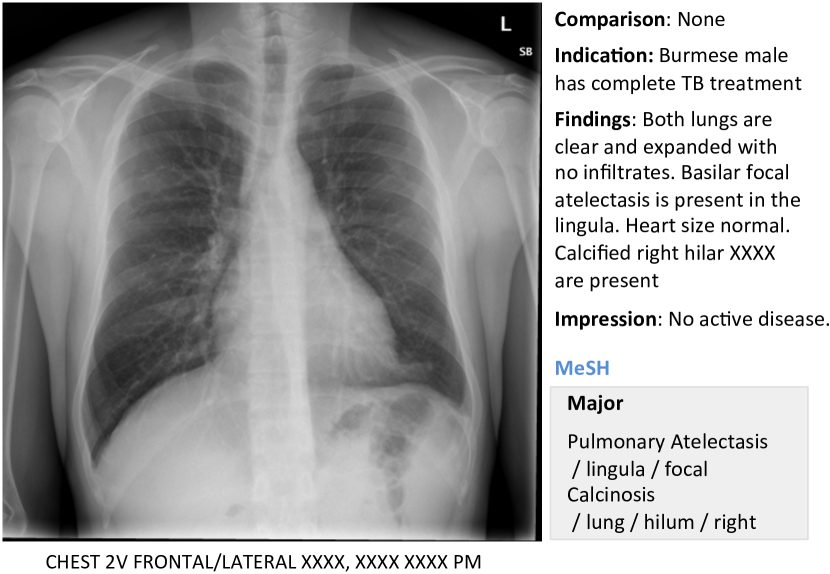

In this work, we demonstrate how to automatically annotate chest x-rays with diseases along with describing the contexts of a disease, e.g., location, severity, and the affected organs. A publicly available radiology dataset is exploited which contains chest x-ray images and reports published on the Web as a part of the OpenI [2] open source literature and biomedical image collections. An example of a chest x-ray image, report, and annotations available on OpenI is shown in Figure 1.

We use a publicly available radiology dataset of chest x-rays and reports that is a subset of the OpenI [2] open source literature and biomedical image collections. It contains 3,955 radiology reports from the Indiana Network for Patient Care, and 7,470 associated chest x-rays from the hospitals’ picture archiving systems. The entire dataset has been fully anonymized via an aggressive anonymization scheme, which achieved 100% precision in de-identification. However, a few findings have been rendered uninterpretable. More details about the dataset and the anonymization procedure can be found in [11], and an example case of the dataset is shown in Figure 1.

Each report is structured as comparison, indication, findings, and impression sections, in line with a common radiology reporting format for diagnostic chest x-rays. In the example shown in Figure 1, we observe an error resulting from the aggressive automated de-identification scheme. A word possibly indicating a disease was falsely detected as a personal information, and was thereby “anonymized” as “XXXX”. While radiology reports contain comprehensive information about the image and the patient, they may also contain information that cannot be inferred from the image content. For instance, in the example shown in Figure 1, it is probably impossible to determine that the image is of a Burmese male.

On the other hand, a manual annotation of MEDLINE ® citations with controlled vocabulary terms (Medical Subject Headings (MeSH®) [1]) is known to significantly improve the quality of the image retrieval results [20, 22, 10]. MeSH terms for each radiology report in OpenI (available for public use) are annotated according to the process described in [12]. We use these to train our model.